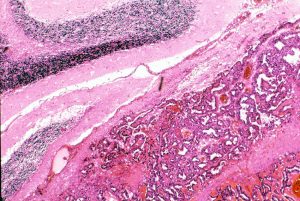

組織学的には,円柱様ないし楕円形の上皮様細胞の網状配列構造を示す腫瘍であり,一部にSchiller-Dubal bodyと呼ばれる血管周囲に集族する特徴的な細胞配列が見られます。これは,一層あるいは多層の上皮様細胞が,中心となる血管をやや離れて取り囲むように並ぶ構造です。また,PAS陽性の好酸性球状体が見られAFPが強陽性となります

視床下部に発生したchoriocarcinomaの病理像(左からHE染色, HCG染色, PLAP染色):腫瘍の大部分にHCG陽性細胞が認められますが,一部ではPLAP陽性のgerminoma細胞様の腫瘍細胞も散見されます。